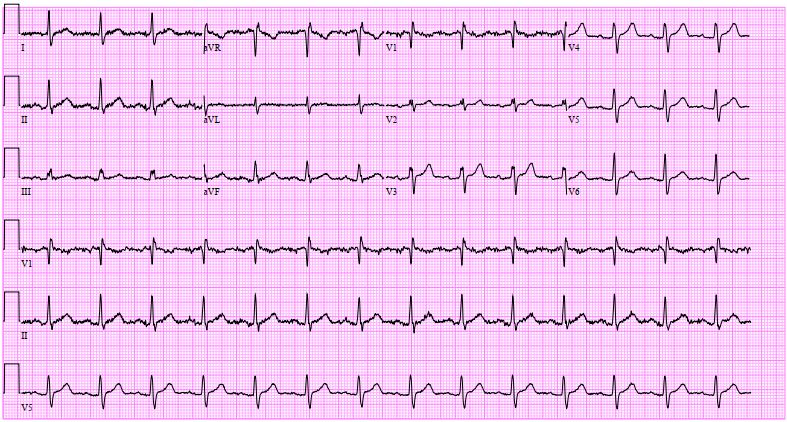

A 57-year-old asymptomatic man underwent a routine chest X-ray revealing perihilar haziness, indicative of pulmonary artery enlargement. A cardiology evaluation revealed a split second heart sound with a loud P2 & a right-sided, pansystolic murmur over the tricuspid area suggest a possible atrial septal defect (ASD) with tricuspid regurgitation. Changes of right heart dilatation like right axis deviation, P-pulmonale & right ventricle hypertrophy are absence in electrocardiography.